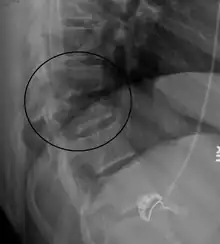

| A Chance fracture of T10 and fracture of T9 due to a seatbelt during an MVC. | |

On plain X-ray, a Chance fracture may be suspected if two spinous processes are excessively far apart.[10]